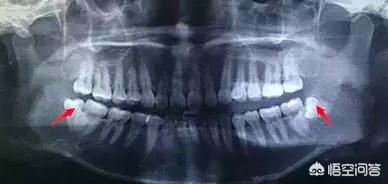

1.若い人や学生で頭痛に悩まされている人は、病院の口内科を受診するか、歯科用フィルムを撮って、頭痛があるかどうかを確認することをお勧めする。障害歯, 親知らず推奨事項がある場合引き出すこれらの歯は異常に生えていたり、深すぎるため、きれいに磨くことが容易ではなく、炎症を繰り返しやすく、しばしば頭痛を誘発する。勉強や仕事、生活にも影響する。